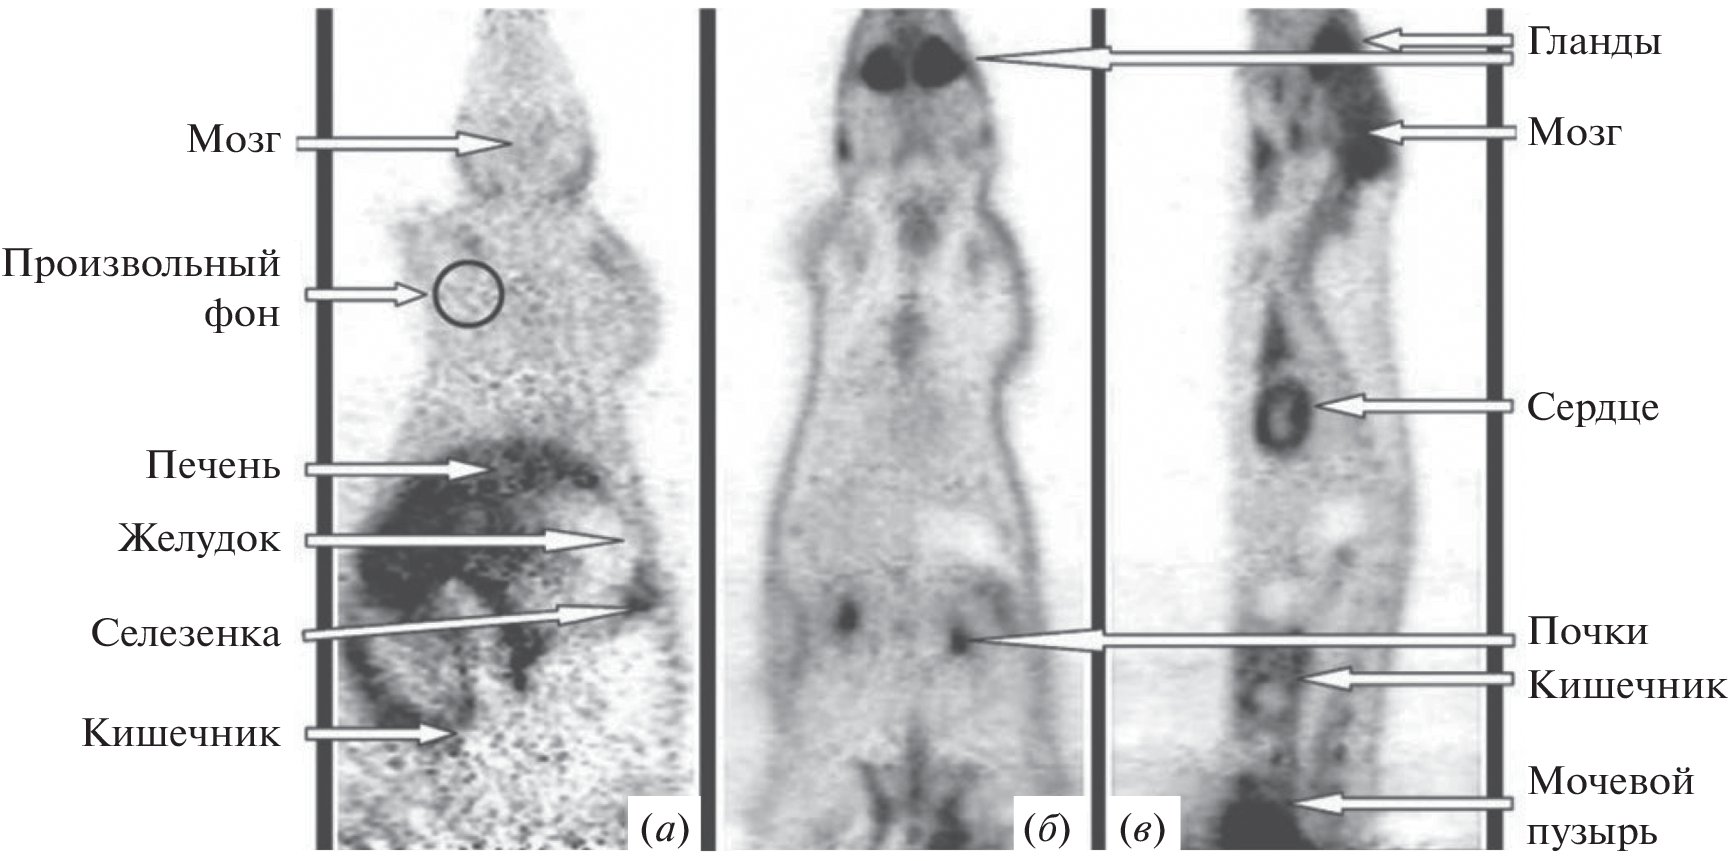

- Blankenberg F.G., Katsikis P.D., Tait J.F., Davis R.E., Naumovski L., Ohtsuki K., Kopiwoda S., Abrams M.J., Strauss H.W. // J. Nuclear Med. 1999. V. 40. P. 184–191.

- Reischl G., Dorow D.S., Cullinane C., Katsifis A., Roselt P., Binns D., Hicks R.J. // J. Nuclear Med. 2007. V. 43. P. 365.